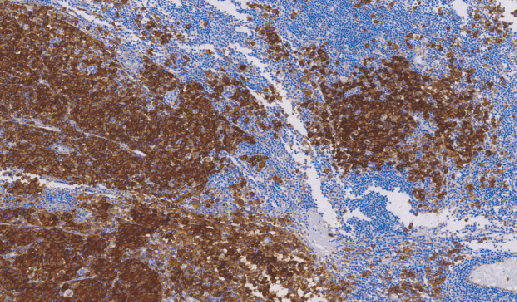

CD63广泛表达于造血和非造血细胞,诸如: 汗腺、Langerhan's岛、垂体、胰腺、支气管周腺体、潘氏细胞和前列腺等细胞中。单核细胞、巨噬细胞、活化的血小板等。CD63作为一种肿瘤抑制基因在恶性黑色素瘤中表达,对其扩散和转移起抑制作用。主要用于恶性黑色素瘤的诊断,但常与NCL-MelanA、NCL-TYROS、NCL-MIFE和NCL-S100p同时检测,以提高准确率。

- 阳性部位:胞膜

- 适用组织:石蜡切片

- 预处理:热修复